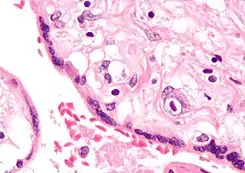

![]() Micrografía de citomegalovirus (CMV) infección de la placenta (placentitis CMV), una infección de transmisión vertical: El característico gran núcleo de una célula infectada con CMV se ve descentrada en la parte inferior derecha de la imagen, tinción H&E. | ||

- Placentitis por citomegalovirus (CMV)